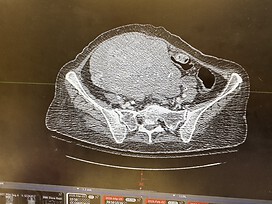

She was dismissed for many years and then went on a surgical journey with little to no success. It is evolved into metastatic ovarian enhancer and she has a 11” x 12” uterine mass fibroid in her abdomen that is out of control. Attached is the tumor of the uterus that fills up her abdomen.